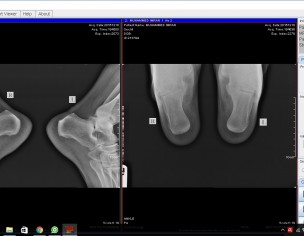

Muhammad Imran from Sharjah suffering both heels pain from last two years here doctor diagnosed PF & also two times inject PF injection but pain is same now some dr says its rehmotoid arthritis & some says no its PF so better to go for Pf Release surgery. kindly help me & advise because pain is worst

kindly confirm me that is it really PF or something else?

Attach Photo here: